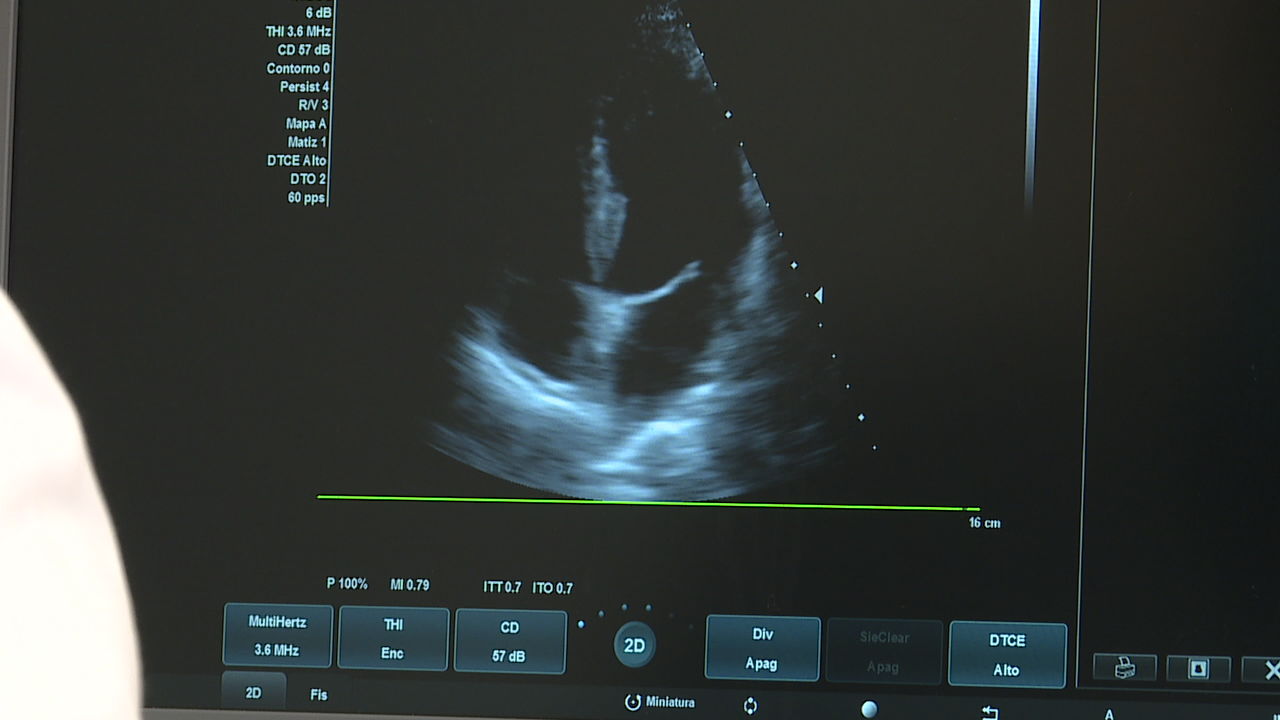

Especialistas en cardioloxía urxen a retomar os controis de doentes crónicos

Especialistas en cardioloxía e cirurxía cardíaca de Santiago, de Coímbra, do Porto e de Salamanca reúnense este sábado en Compostela. Desenvolven proxectos de investigación conxunta e comparten experiencias e necesidades de melloras na atención asistencial.

Poñen de manifesto a importancia de recuperar, despois da pandemia, a continuidade asistencial no seguimento dos pacientes crónicos.